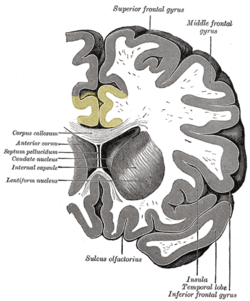

قطاع إكليلي للمخ. القشرة الحزامية موضحة الأصفر.